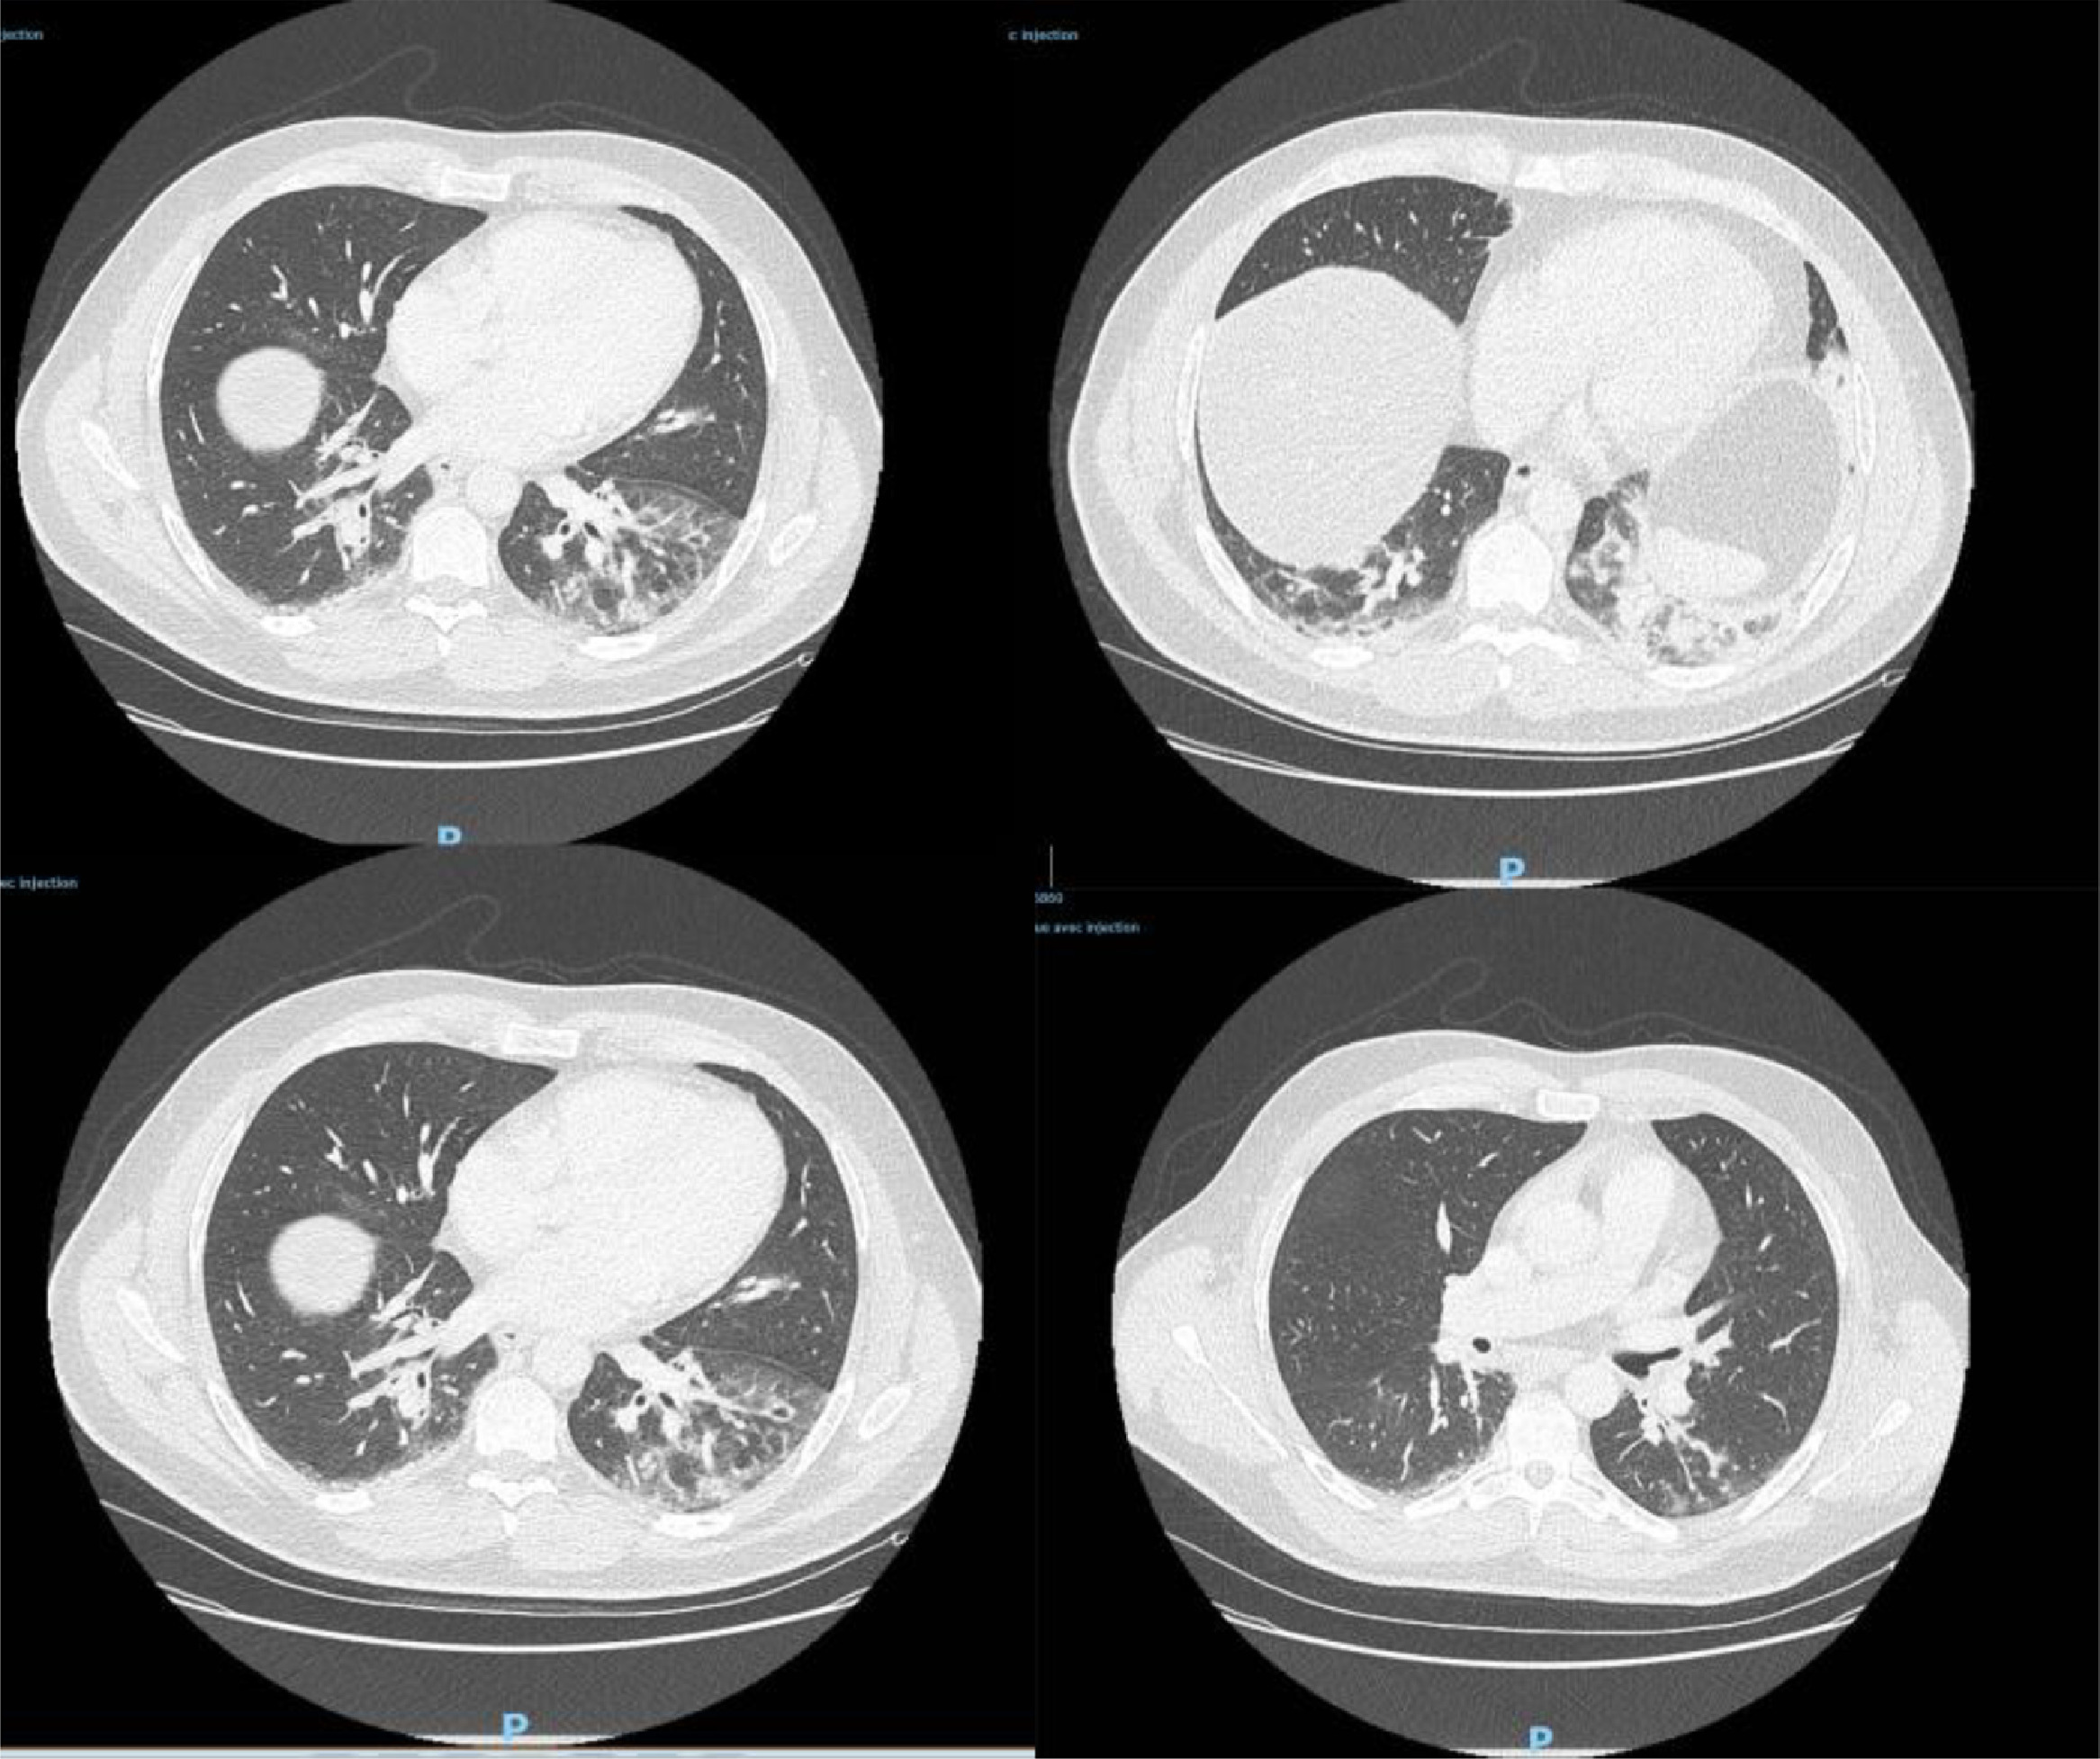

据了解,患者去年12月27日到急诊室就医,CT检查显示双侧肺下叶呈现磨玻璃影,并伴有咯血、咳嗽、头痛及发热症状,且当时症状已持续4天。病患当天被收入重症监护室并接受抗生素治疗,后因病情好转于12月29日解除重症监护。

△图为病患CT检测影像